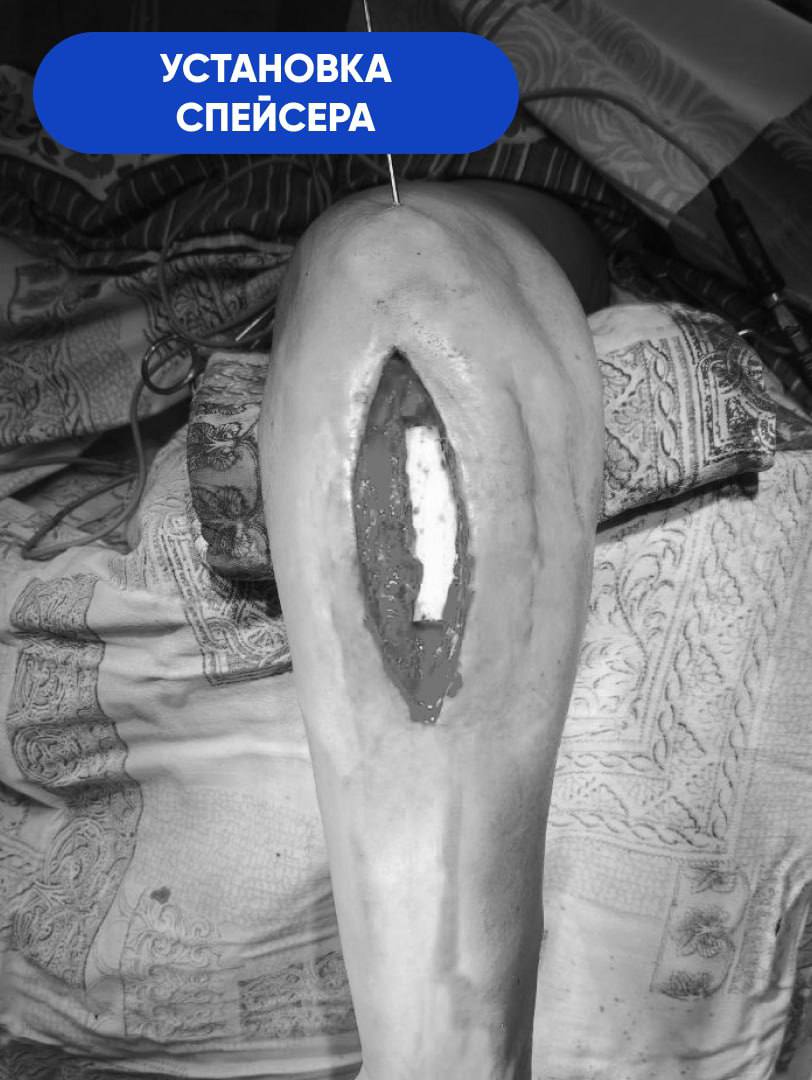

-В первую очередь нам необходимо было справиться с инфекцией. При свищевом остеомиелите ждать результата от обычной антибактериальной терапии бессмысленно. Воспалительный процесс разрушил кость на участке длиной 8 сантиметров. Этот фрагмент подлежал удалению в пределах здоровых тканей. На его место установили спейсер из антибиотика и костного цемента. Мы изготовили его самостоятельно в условиях операционной, по собственной технологии и индивидуальным размерам. Имплантат выполнял двойную задачу. Во-первых, это источник антибиотика в непосредственном очаге заражения. Во-вторых,- механическая поддержка для кости за счёт своей армирующей функции, - объясняет Сергей Глиняный.

Благодаря профессионализму и смекалке врачей, ещё на этапе лечения остеомиелита пациент впервые вновь начал двигать рукой и приступил к её разработке. Спейсер, зафиксированный на участке недостающего костного фрагмента, создавал эффект целостности кости на протяжении всех двух месяцев антибактериальной терапии. Однако самый ответственный этап был впереди.